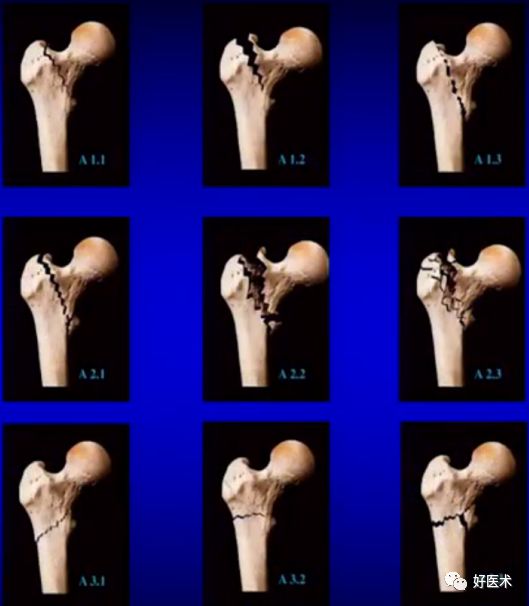

3.AO分类

--股骨粗隆间骨折35.7%(31-A1/A2)

--股骨粗隆间反向骨折7.3%(31-A3)

--股骨粗隆下骨折3.2%